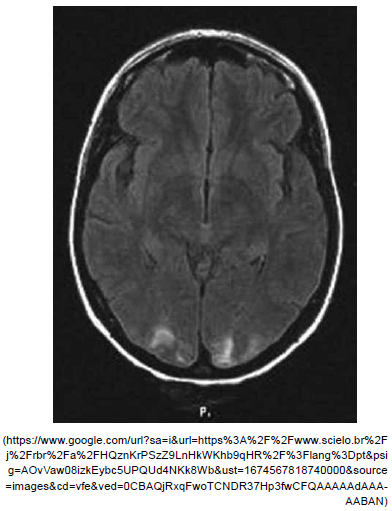

Paciente feminina, 32 anos, em sua segunda gestação com aumento dos níveis pressóricos no terceiro trimestre e no trabalho de parto, após 5 dias de puerpério foi admitida no hospital com quadro de diminuição de acuidade visual à esquerda, crise convulsiva tônico-clônica generalizada e sonolência. Realizada a ressonância de crânio a seguir.

Assinale a alternativa correta referente ao diagnóstico mais provável dessa paciente.